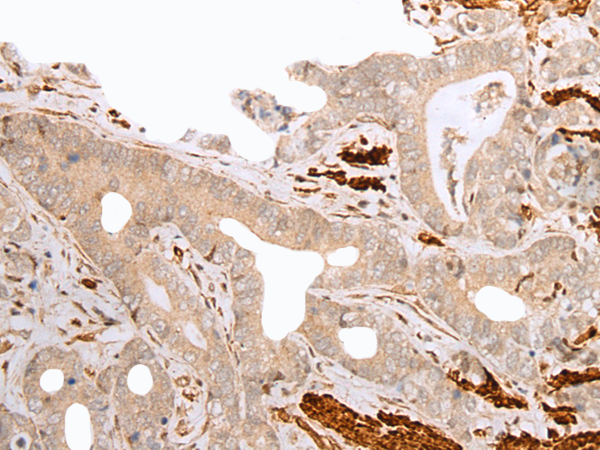

The image is immunohistochemistry of paraffin-embedded Human breast cancer tissue using P05661(GFRA4 Antibody) at dilution 1/20. (Original magnification: ×200) |